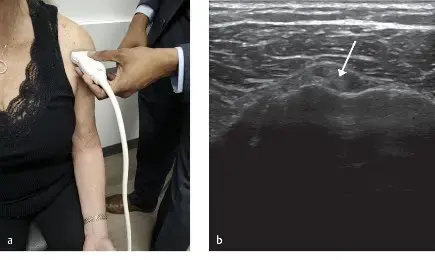

الشكل 1:

إعادة بناء ثلاثية الأبعاد بالتصوير المقطعي المحوسب للكتف الأيمن، تظهر كسرًا في عنق العضد الجراحي من نوع Neer 2-part. يظهر خط الكسر عبر عنق العضد الجراحي مع إزاحة طفيفة. كما تم تحديد ميزات تشير إلى خلع أمامي تم رده (آفة هيل-ساكس، آفة بانكارت العظمية) عند التحليل التفصيلي للشرائح.